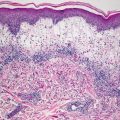

The histologic findings of acropustulosis of infancy are not specific, but characteristic of this entity. The epidermis has foci of spongiosis with microvesiculation [2] (Fig. 3.3). Neutrophilic abscesses are present within the vesicles (Fig. 3.4). Acute lesions do not have parakeratosis, although this is a common finding in more established lesions. Less commonly, eosinophils may be present within the microvesicles [3].

Fig. 3.4

Subcorneal neutrophilic clusters are present in acropustulosis of infancy